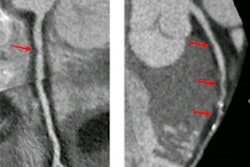

Cardiovascular disease includes coronary heart disease, stroke, high blood pressure, circulatory system disease, and other vascular/arterial disease.